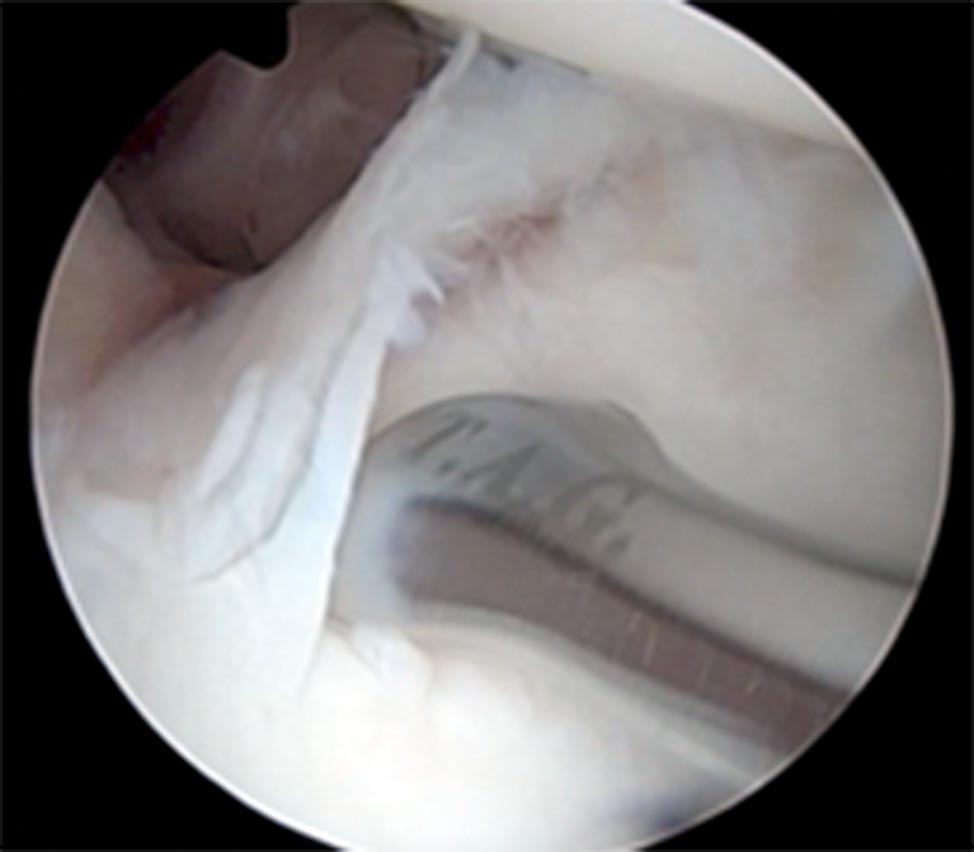

En el sector posterior se evidencia una elongación capsular postero-inferior, con avulsión de labrum posterior en igual sector (fig. 2).

Posteriormente colocamos una cánula fina en el portal posterior, el portal antero-superior pasa a ser de visión y el posterior de trabajo.